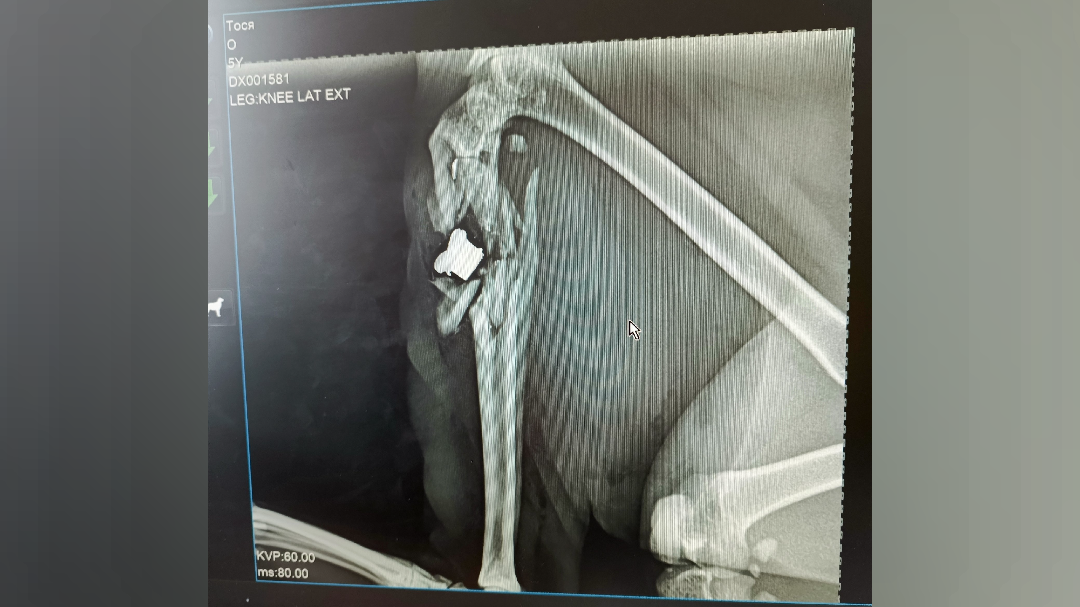

Как уточнили в сети, в Сортавале неизвестный ранил кошку из пневматического оружия — теперь у животного оскольчатый перелом лапы.

Раненую кошку доставили в Санкт-Петербург на операцию, где ветеринары установили животному металлическую конструкцию. Теперь кошке предстоит длительная реабилитация, сообщили хозяева животного.

фото: © Подслушано в Сортавала / ВК